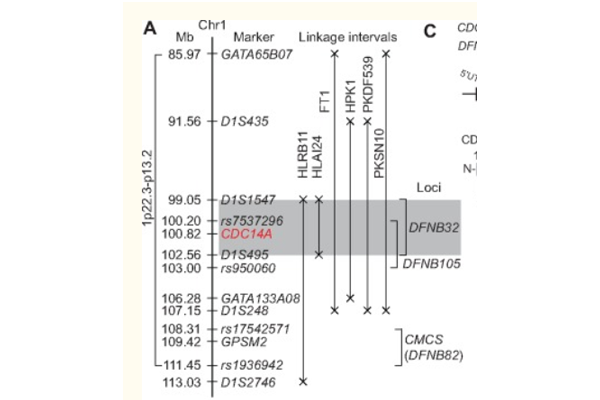

CDC14A基因是一种进化/保守的双特异性蛋白磷酸酶,在不同的生物体中发挥不同的作用。据报道,人类CDC14A突变可导致男性不育和女性先天性耳聋,CDC14A缺陷...